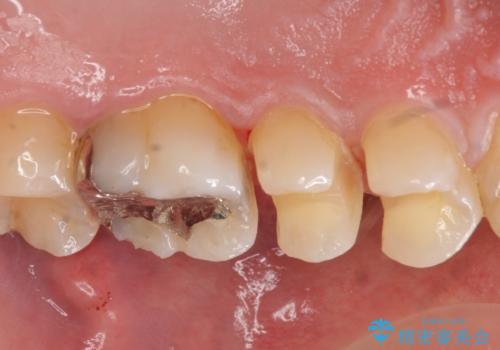

コンタクトカリエスの治療

- 虫歯の検査のために来院された患者さまです。

レントゲンで診査したら、歯と歯の間に虫歯(コンタクトカリエス)が見られたので

e-maxインレーで治療を行いました。